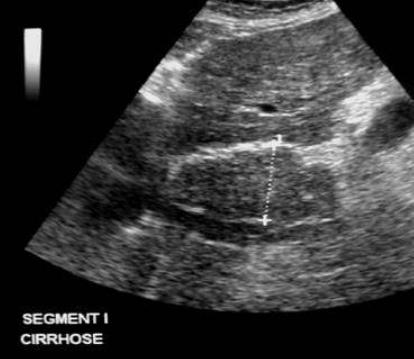

Au stade precoce de

cirrhose biliaire du foie image

echographique est hypertrophie a

hypoechogene du lobe caudal du foie . Image

echographique en coupe sagital de la ligne

mediane . |